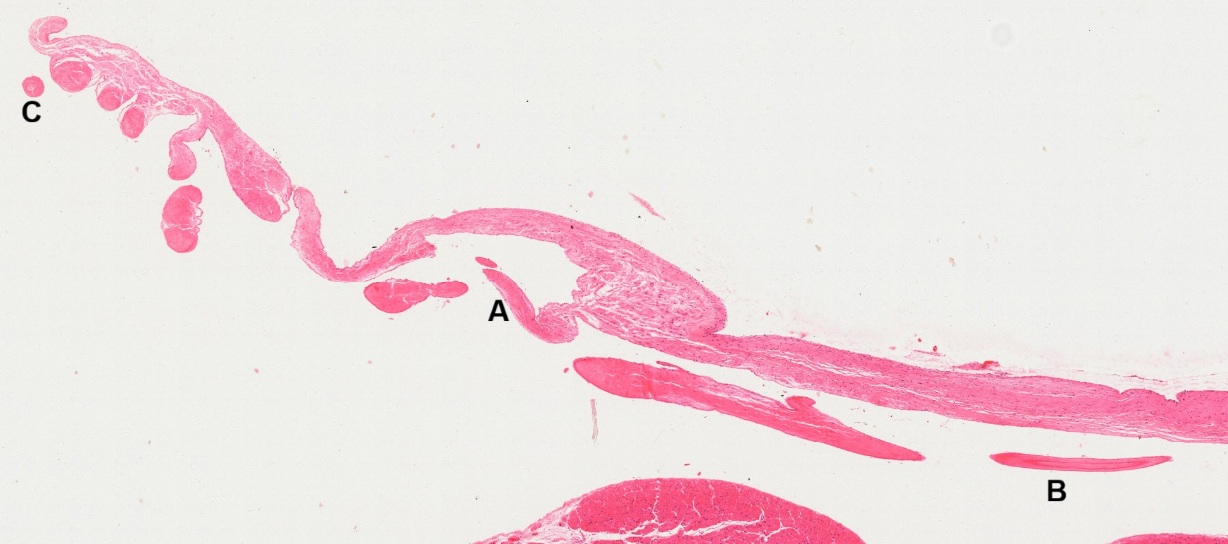

To observe histological composition of the chordae tendineae, micrographs are taken from three spots (Fig. 8-34): A. longitudinal section of an attached segment on the mitral valve (Fig. 8-35); B. longitudinal section of a terminal segment unattached on the valve (Fig. 8-36); C. transverse section of a free segment (Fig. 8-37).

All three segments of chordae tendineae are encapsulated by a layer of endothelial cells. The attached segment (Fig. 8-35) is composed of dense regular connective tissue (DR) in the middle surrounded by loss connective tissue (LC) and dense irregular connective tissue (DI). The free segment (Fig. 8-36) is composed of dense regular connective tissue only, which is similar to composition of ligament. The unattached terminal segment (Fig. 8-37) shows a central core (C) surrounded by layers of circular fibrous connective tissue.